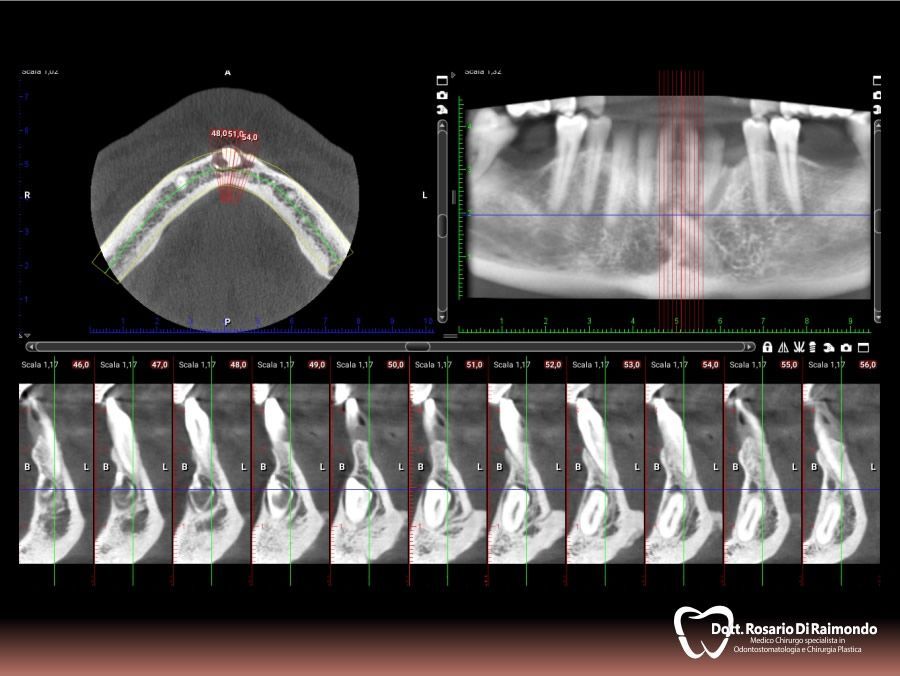

Casi Trattati

Di seguito riportiamo alcune fotografie di casi esplicativi di Chirurgia Orale.